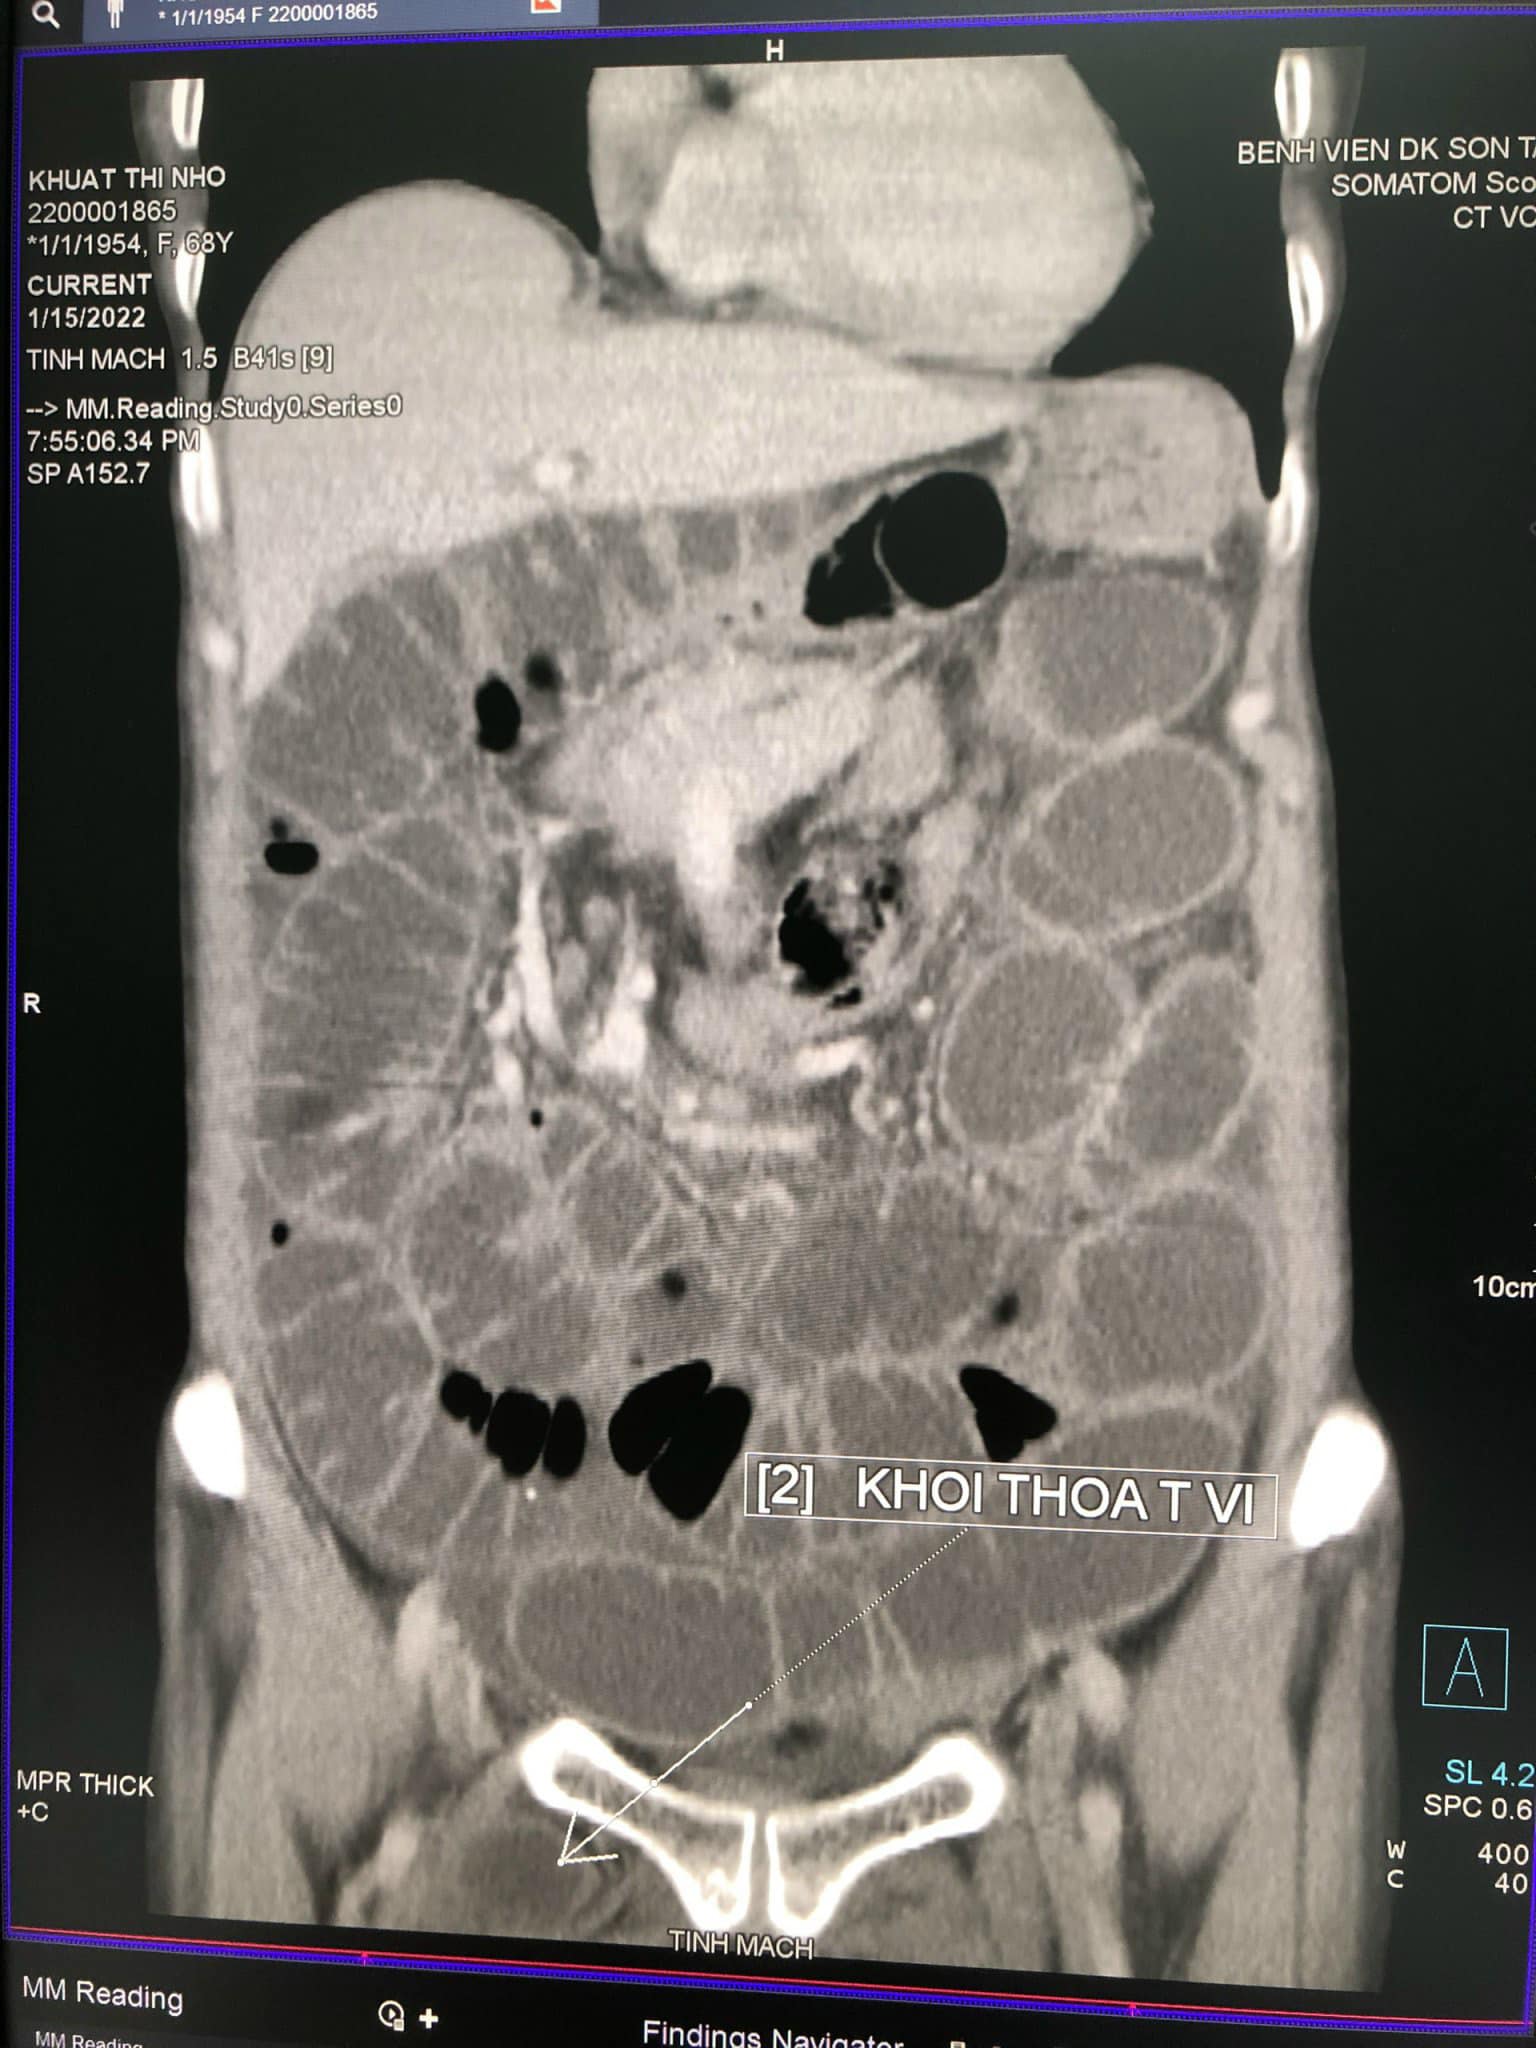

Qua thăm khám, thực hiện chụp cắt lớp vi tính (CT) phát hiện có quai ruột non chui qua và kẹt ở lỗ bịt bên phải, các quai ruột non giãn, đường kính từ 27-30mm. Tiến hành hội chẩn, các bác sĩ xác định bệnh nhân bị thoát vị bịt bên phải nghẹt, chỉ định mổ cấp cứu.

Bệnh nhân Khuất Thị N đã được bác sĩ khoa Ngoại Tổng hợp, khoa Chẩn đoán hình ảnh, khoa Gây mê và Hồi sức cấp cứu Bệnh viện đa khoa Sơn Tây phát hiện và phẫu thuật cấp cứu kịp thời. Quá trình phẫu thuật ghi nhận các quai ruột giãn to, nhiều dịch. Quai ruột cách góc Treizt khoảng 40cm chui vào lỗ bịt bên phải gây hoại tử ruột. Tiến hành giải phóng quai ruột nghẹt, khâu lại lỗ bịt. Cắt đoạn ruột hoại tử, đầu trên cách góc Treizt 20cm xét thấy phải nối ngay không thể làm hậu môn nhân tạo được. Kíp phẫu thuật đã phải nối ruột bên bên luôn.